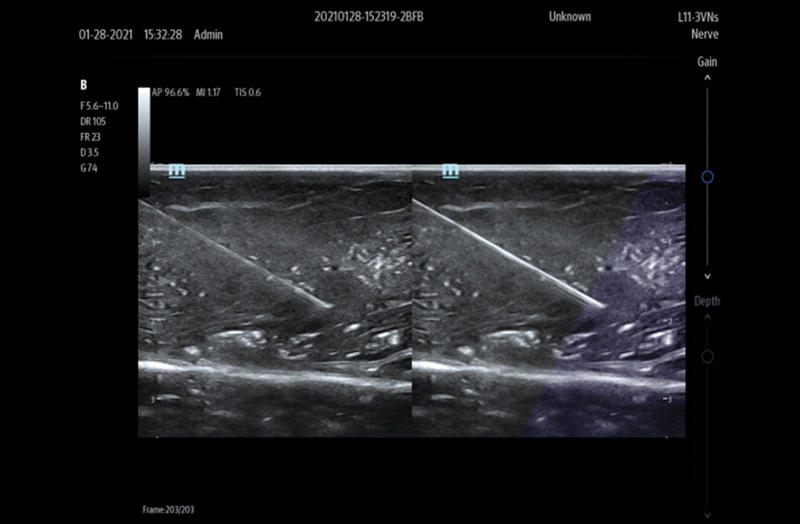

Needle Guidance

Clinical Images